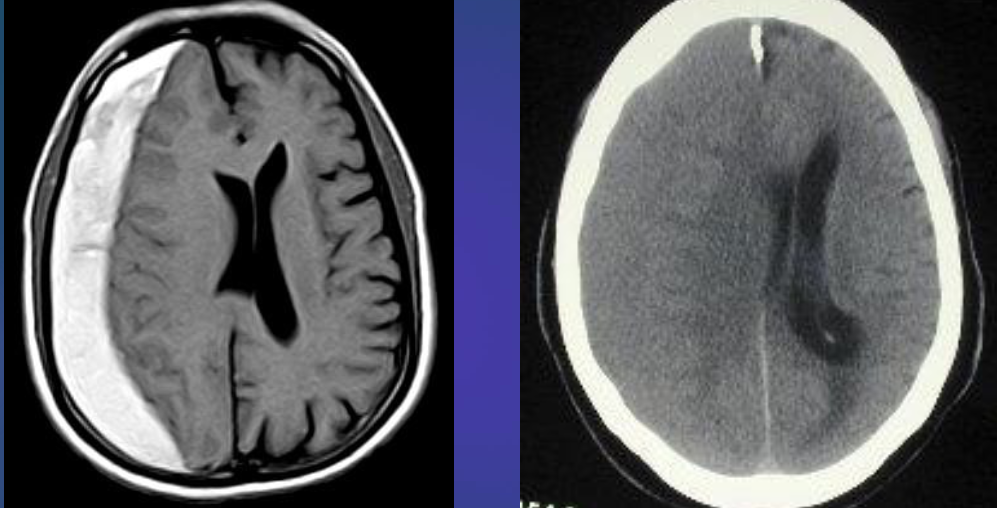

Patients presents with optic neuritis

(a) Axial FLAIR sequence at the level of the lateral ventricles

- shows periventricular areas of linear and ovoid hyperintense

- signal orientated perpendicular to the body of the right lateral ventricle. This feature is known as Dawson fingers and is

- strongly associated with multiple sclerosis.

(b) Parasagittal T2-weighted MRI

- shows plaques of demyelination as high signal in the white matter, particularly along the

- margins of the lateral ventricles

Modality MRI Findings Plaques of demyelination, dawson fingers Diagnosis multiple sclerosis

CT brain - Hydrocephalus

Axial T2-weighted MRI - Cerebral atrophy

showing prominence of the ventricles and generalized widening of

the cerebral sulci in keeping with age-related atrophy.